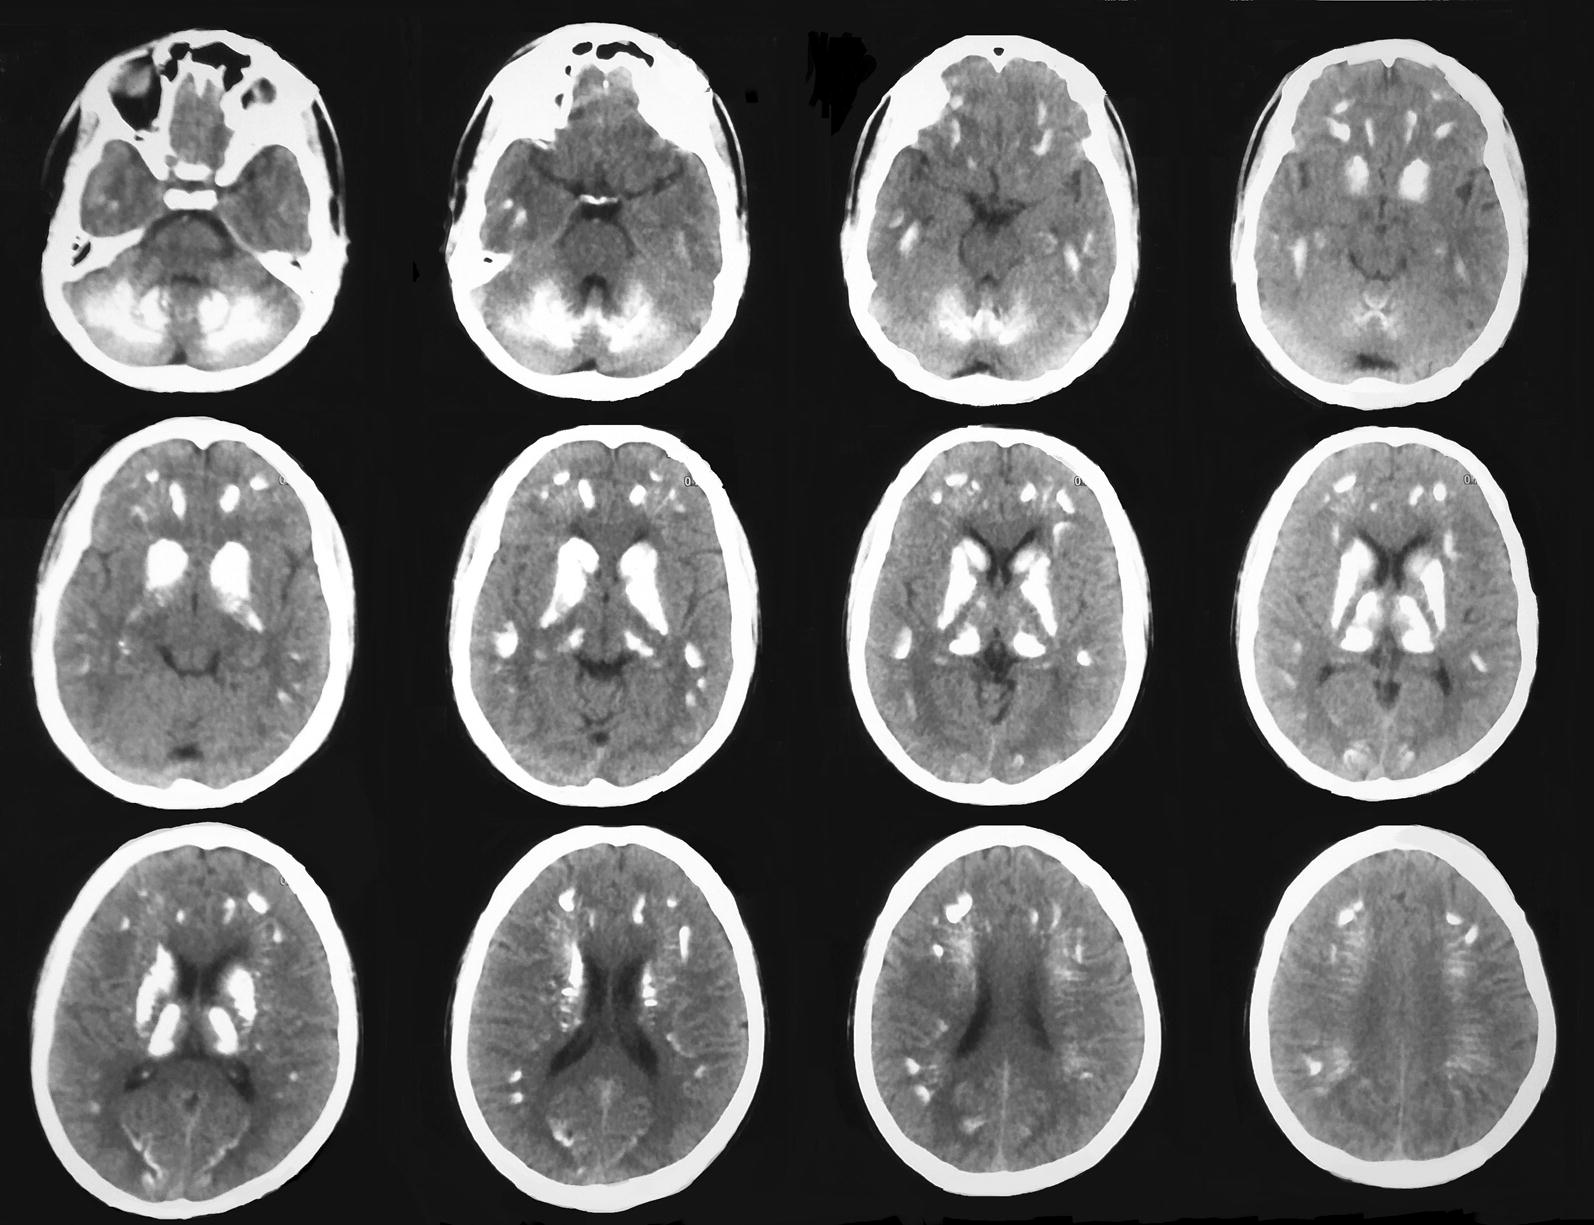

Non contrast computed tomography (NCCT) scan of the brain revealed multiple basal ganglia, subcortical and cerebellar calcifications (Fig. 1).

Fig. 1.

NCCT of brain. Bilateral symmetrical calcifications in cerebral subcortical regions, basal ganglia and cerebellum mainly involving biventral and semilunar lobules and posterior vermis